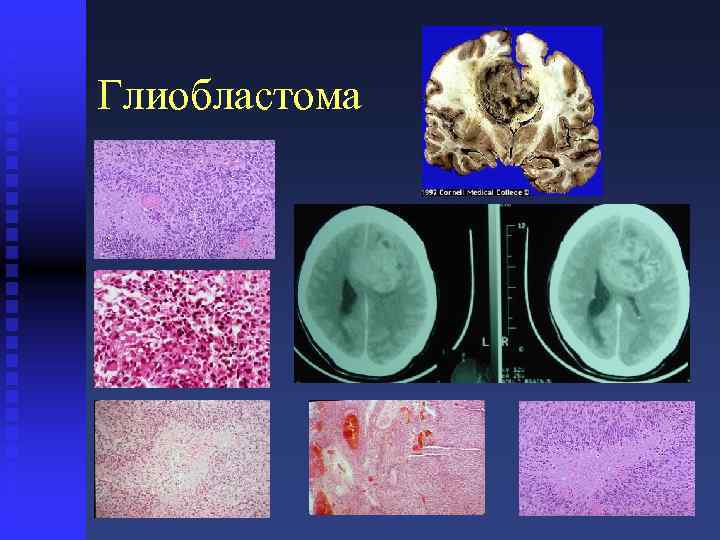

Микрофотографии гистологии глиобластомы головного мозга